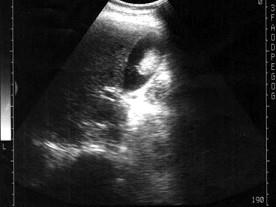

问题 患者男56岁,上腹部不适1年余,B超检查如图所示,根据超声声像图,诊断为?(?)

选项 A.胆囊结石 B.胆囊息肉 C.胆囊癌 D.胆囊腺瘤 E.胆囊腺肌瘤

答案 D